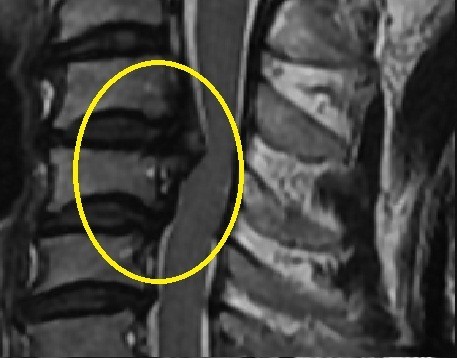

후종인대 골화증은 척추의 뒤쪽에 있는 후종인대가 뼈처럼 단단해지면서 척추관을 좁히거나 신경을 압박하는 질환입니다. 후종인대는 척추뼈 사이를 연결하는 인대로, 척추의 안정성을 유지하는 역할을 합니다. 후종인대 골화증은 주로 경추에서 발생하며, 흉추와 요추에서도 발생할 수 있습니다.